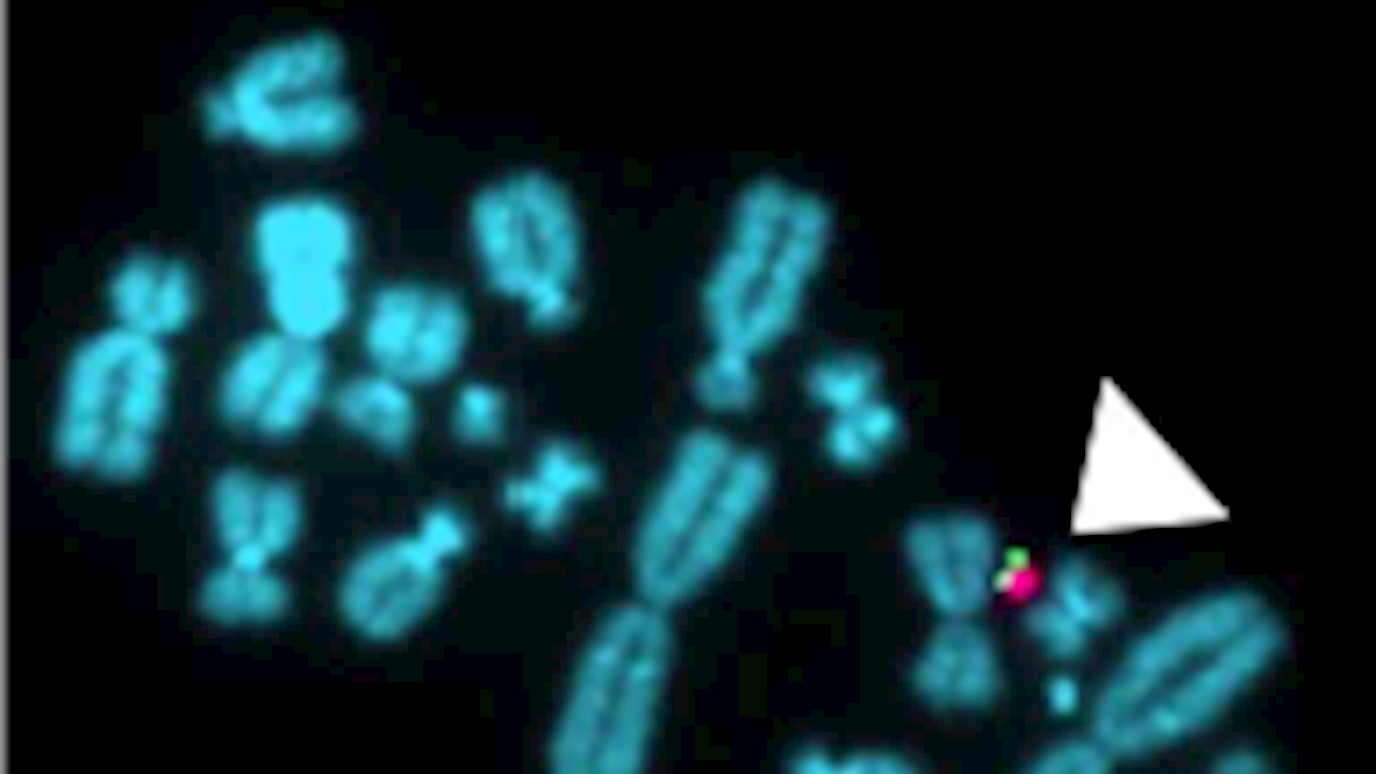

Microscopic image of the small artificial human chromosome (white arrowed, red and green element) among other natural chromosomes (blue).

Scientists at Royal Holloway, University of London, along with colleagues at UCL, have developed a novel artificial human chromosome which could be used to reverse the genetic defect in muscle stem cells from patients with Duchenne muscular dystrophy (DMD).

The current study, carried out by Professor George Dickson and Dr Linda Popplewell from the School of Biological Sciences, in collaboration with Dr Saverio Tedesco and colleagues at UCL, focused on the genetic correction of DMD muscle stem cells using gene therapy to develop this novel artificial chromosome system.

The researchers used an entirely man-made chromosome that contains a dystrophin gene, which works as part of a group of proteins to strengthen muscle fibres and protect them from injury and act as an anchor, connecting each muscle cell’s structural framework with the lattice of proteins and other molecules outside the cell.